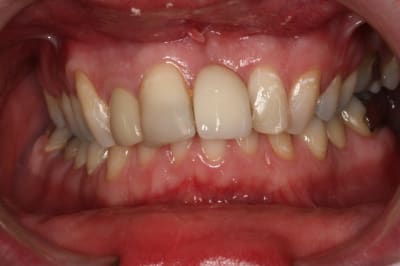

Les lésions cervicales sont probablement des abfractions, son occlusion est en cause.

Montre nous une photo en occlusion.

Les caries multiples au collet sont peu fréquentes

Angulation des dents très lingualée, molaires inférieures avec manque d'éruption.

overbite et Cl-2 ??

Je suggère ortho, chirurgie paro, céram

pour l'occlusion, voilà les photos, il y a effectivement une classe II, plus marquée à droite qu'à gauche

il y a l'absence de la 36 depuis quasiment l'enfance, l'occlusion est calée comme ça depuis plus de 30 ans et ça ne bouge pas

il n'y a pas (ou peu) de supraclusion (overbite je crois que c'est ça)

il n'y a aucun problème musculaire ou articulaire

niveau paro si je dis que c'est stable c'est qu'il n'y a pas de poches

quand je disais qu'il faut faire gaffe, c'est que c'est effectivement le risque chez cette patiente avec le parodonte fin mais elle fait attention à ses dents, suis les conseils et viens régulièrement depuis que je la suis (même si nous n'avons pas d'hygiènistes mais c'est un autre débat)

elle a certes un sourire très gingival lié à la classe II, mais est-ce si grave que ça ?